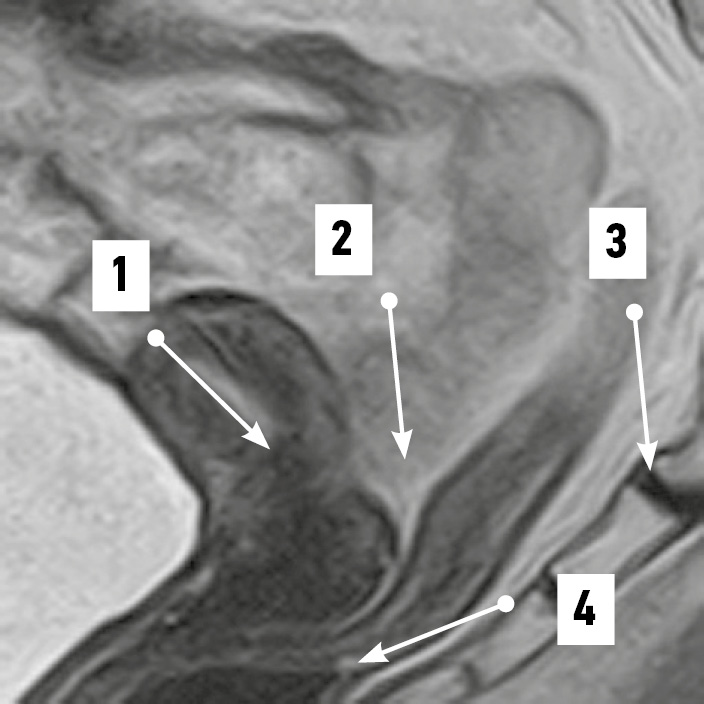

Рис. 1. Извитой во фронтальной плоскости надвлагалищный участок прямой кишки. Магнитно-резонансная томограмма органов таза в режиме SG T2: 1 — матка; 2 — надвлагалищный участок прямой кишки (извит во фронтальной плоскости); 3 — влагалищный участок прямой кишки; 4 — крестец; 5 — прямокишечно-маточное пространство. / Fig. 1. Supravaginal segment of the rectum convoluted in the frontal plane. SG T2-magnetic resonance imaging of pelvic organs: 1 — uterus; 2 — supravaginal segment of the rectum (convoluted in the frontal plane); 3 — vaginal segment of the rectum; 4 — sacrum; 5 — rectal–uterine space.

По результатам МРТ-анализа при положениях матки anteversio-anteflexio надвлагалищный участок прямой кишки в половине случаев (52,4%) был извит во фронтальной плоскости (рис. 1). В 38,1% случаев кишка имела ход, соответствующий вогнутости крестца (рис. 2), ещё в 9,5% сагиттальный изгиб кишки был значительно выражен. Расстояние между маткой и прямой кишкой в надвлагалищном участке в среднем составило 5,93±0,97 мм. Здесь прослеживался значительный разброс минимальных и максимальных величин, свидетельствовавший о разнообразии положения органов: от их крайней степени близости — 0,00 мм (рис. 3) до удалённого положения — 17,00 мм (рис. 4). Последнее может служить анатомической предпосылкой для положения петель тонкой кишки в относительно широком прямокишечно-маточном углублении.